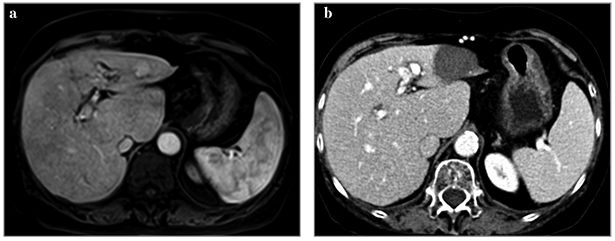

TACE clasic este realizat prin livrarea medicamentelor citotoxice în emulsie cu ulei iodat (lipiodol) și embolizarea vaselor arteriale nutritive cu gelaspon sau tipuri variate de particule. Procedura a fost utilizată timp de peste 20 de ani, cu rezultate bune în tratamentul CHC (fig. 1).

VM 25, p.12-13 - 1

Fig. 1 - a) Angiografie hepatică cu evidenţierea unui nodul tumoral în segmentele V-VI; b) și c) examinarea CT efectuată pre și postprocedural, cu vizualizarea prizei de lipiodol la nivelul nodulului